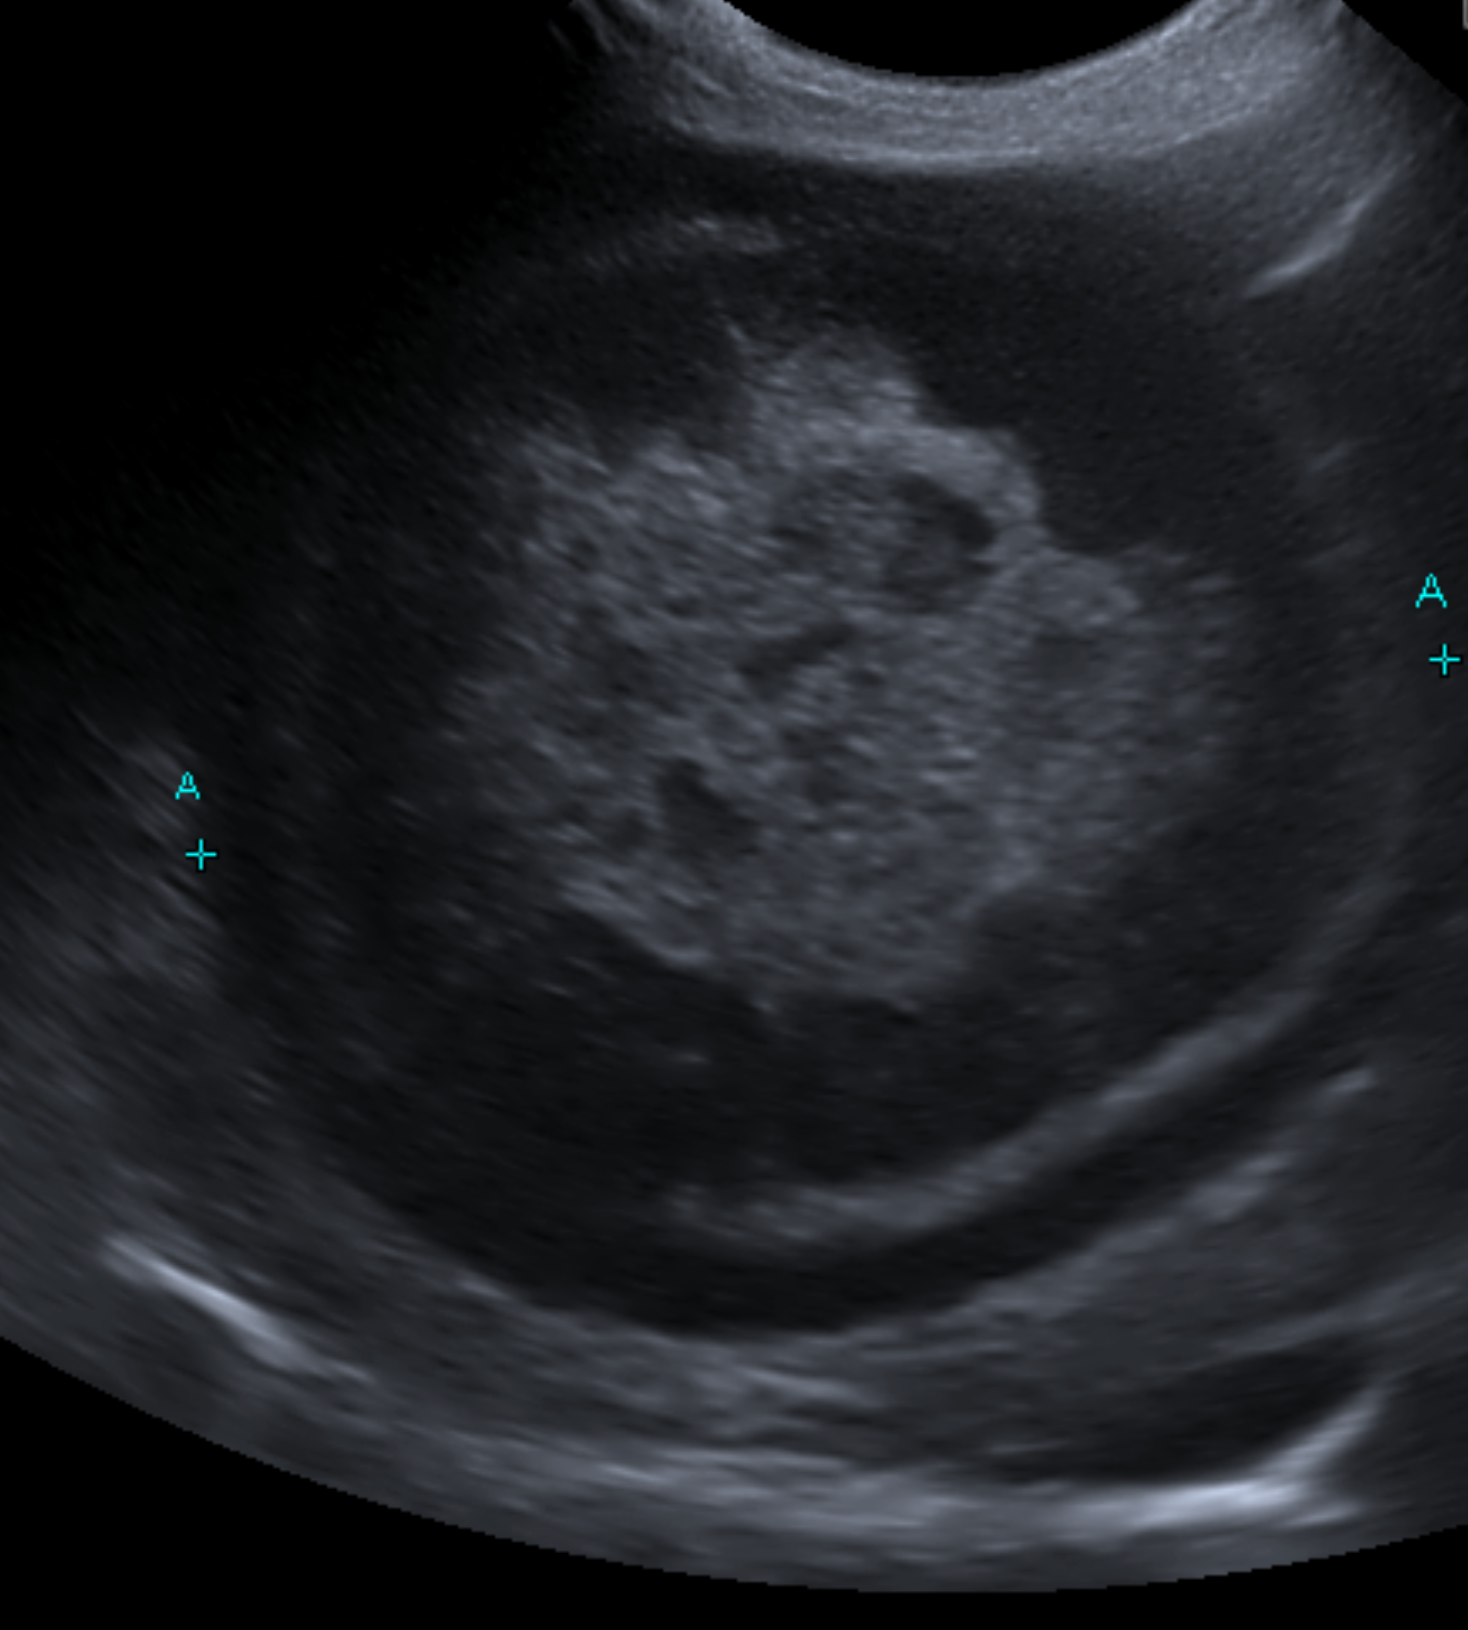

血液検査においては肝数値の上昇、T-Bilの上昇、超音波画像検査においてはキウイフルーツの様な特徴的な胆嚢の内腔の見え方を示します。

超音波画像を示します。

こちらが典型的なキウイフルーツ様を示す胆嚢です。